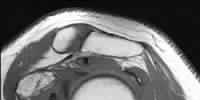

Question 8

A 31-year-old volleyball player presents with deep posterior shoulder pain. MRI arthrogram reveals a posterior labral tear with an associated large paralabral cyst extending into the spinoglenoid notch. Clinically, this patient is most likely to exhibit which of the following isolated motor deficits?